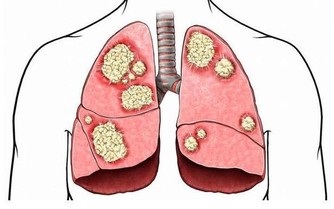

醫學上,胰腺癌是一種惡性程度很高,診斷和治療都很困難的消化道惡性腫瘤,約90%為起源於腺管上皮的導管腺癌。其發病率和死亡率近年來明顯上升。5年生存率<1%,是預後最差的惡性腫瘤之一,正因如此,人們將其稱為癌症之王!胰腺癌早期的確診率不高,手術死亡率較高,而治愈率很低。本病發病率男性高於女性,男女之比為1.5~2:1,男性患者遠較絕經前的婦女多見,絕經後婦女的發病率與男性相仿。

胰腺癌的病因尚不十分清楚。但大量的流行病學數據顯示,它的發生與吸煙、飲酒、高脂肪和高蛋白飲食、過量飲用咖啡、環境污染及遺傳因素有關;近年來的調查報告發現糖尿病人群中胰腺癌的發病率明顯高於普通人群;也有人注意到慢性胰腺炎病人與胰腺癌的發病存在一定關係,發現慢性胰腺炎病人發生胰腺癌的比例明顯增高;另外還有許多因素與此病的發生有一定關係,如職業、環境、地理等。

其實胰腺癌早期症狀非常隱匿,可能只是輕微的腹痛腹脹,很多患者常常把胰痛當做胃痛,直到出現很嚴重的症狀時,才會來醫院就診,可是往往已喪失手術機會。